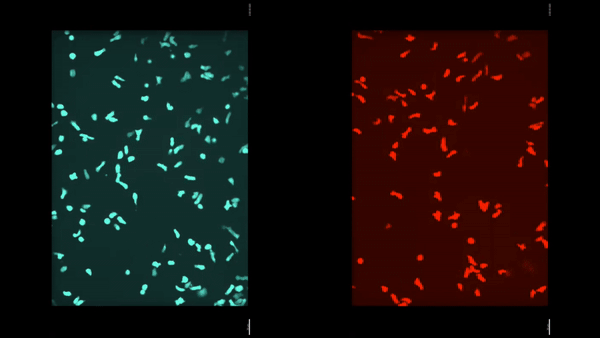

ASB2α-proficient (cyan) and ASB2α-deficient (red) Th2 lymphocytes seeded onto vitronectin-coated slides were imaged by time-lapse microscopy.